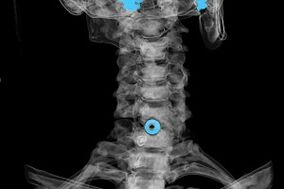

La diagnosi viene fatta sulla base dei sintomi caratteristici e sulla base di:

- Raggi X. Il metodo è inefficace, soprattutto nelle fasi finali dello sviluppo dell'osteocondrosi.

- MRI (risonanza magnetica) del rachide cervicale. Un metodo che permette di vedere le strutture ossee, le ernie discali, la loro dimensione e direzione di sviluppo.

- Tomografia computerizzata. Una soluzione meno efficace della risonanza magnetica perché la presenza e la dimensione delle ernie sono difficili da determinare.